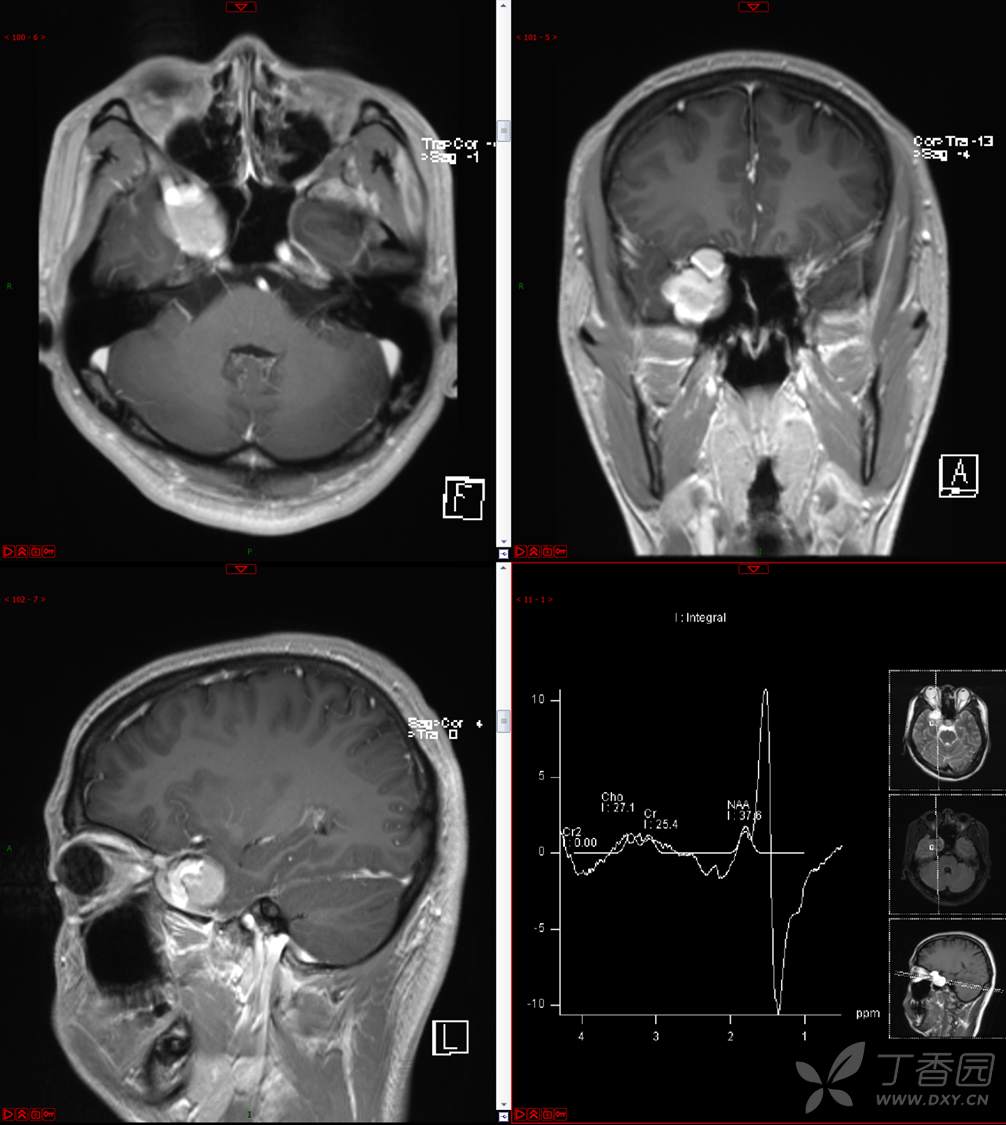

【影诊笔记534】青年男性,视物模糊就诊,CT、MRI、MRS齐全,请分析~~~

主 诉:视物重影5天。

现病史:患者5天前无明显诱因出现视物重影,表现为右视时视物成双,无头痛、头晕,无恶心、呕吐,无面部麻木、饮水呛咳等,于当地医院就诊,行颅脑MR示“颅内占位性病变”,现为求进一步治疗来诊。患者病来精神可,饮食、睡眠正常,体重无明显变化。